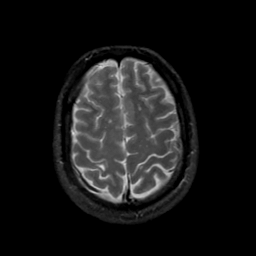

MR Study #17, July 7, 1991 -- Slice #40